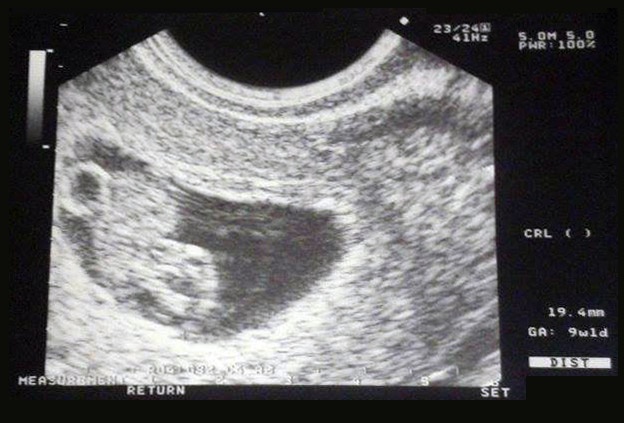

Viszont a kis Tündérkémmel minden a legnagyobb rendben, már amit láttam a monitoron, olyan kis bájosan ücsörgött a pocakomban! Akkor volt 9 hetes +1 napos, tehát most már 10 hetes! Meghallgattuk a szívverését is, szóval köszöni szépen, él és virul. Már csak az anyukáját kéne hagynia virulni....

Bejelentkeztem már a 12. heti ultrahangra, ami már csak 2 hét, ráadásul most tudatosult bennem, hogy pont a névnapomon megyek! Remélem, apa is el tud velem jönni.